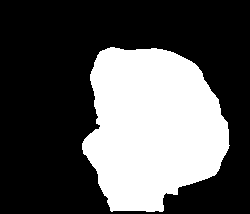

A few sample images and the corresponding masks of the polyp dataset in HyperKvasir are shown in Fig 2. The polyp images are RGB images. The masks of the polyp images are single-channel images with white () for true pixels, which represent polyp regions, and black () for false pixels, which represent clean colon or background regions. In this dataset, there are different sizes of polyps. The distribution of polyp sizes as a percentage of the full image size is presented in the histogram plot in Fig 3, and we can observe that there are more relatively small polyps compared to larger polyps. Additionally, a subset of this dataset was used to prove that the performance of segmentation models trained with small datasets can be improved using our SinGAN-Seg pipeline, and the whole dataset was used to show the effect of using SinGAN-Seg generated synthetic images instead of a large dataset which has enough data to train segmentation models. In this regard, this dataset was used for two purposes:

After training SinGAN-Seg models, we generated random samples per real image using the input scale , which is the lowest scale that uses a random noise input instead of a re-scaled input image. For more details about these scaling numbers and corresponding output behaviors, please refer to the vanilla SinGAN paper [56]. Three randomly selected training images and the corresponding first synthetic images generated using scale are depicted in Fig 4. The first column of the figure represents the real images and the ground truth mask annotated from experts. The rest of the columns represent randomly generated synthetic images and the corresponding generated mask.

In total, we have generated synthetic polyp images and the corresponding masks. SinGAN-Seg generates random samples with high variations when the input scale is . This variation can be easily recognized using the standard deviation (SD) and the mean mask images presented in Fig 5. The mean and SD images were calculated by stacking the generated mask images corresponding to the synthetic images related to a real image and calculating pixel-wise std and mean. Bright color in std images and dark color in mean images mean low variance of pixels. In contrast, dark color in std and bright color in mean images reflect high variance in pixel values. By investigating Fig 5, we see that small polyp masks have high variance compared to the large polyp mask as presented in the figure.